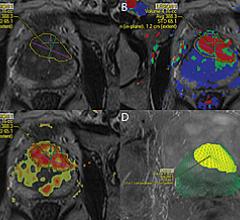

August 14, 2014 — Oncologists at UC San Diego Moores Cancer Center are the first in San Diego to meld magnetic resonance imaging (MRI) technology with a traditional ultrasound prostate exam to create a 3-D map of the prostate that allows physicians to view growths that were previously undetectable.